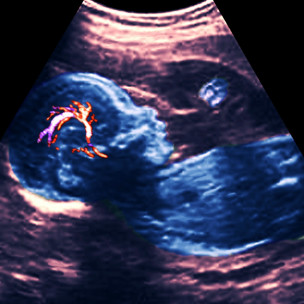

一種常見的先天血管缺陷是「腦動靜脈血管畸形」(anarteriovenous malformation 簡稱AVM)。

專家稱,這種在胚胎期形成的缺陷會使動脈血在不經過毛細血管的情況下直接注入靜脈,並可能在高速高壓注入時形成血液短路,並最終導致腦出血和中風。